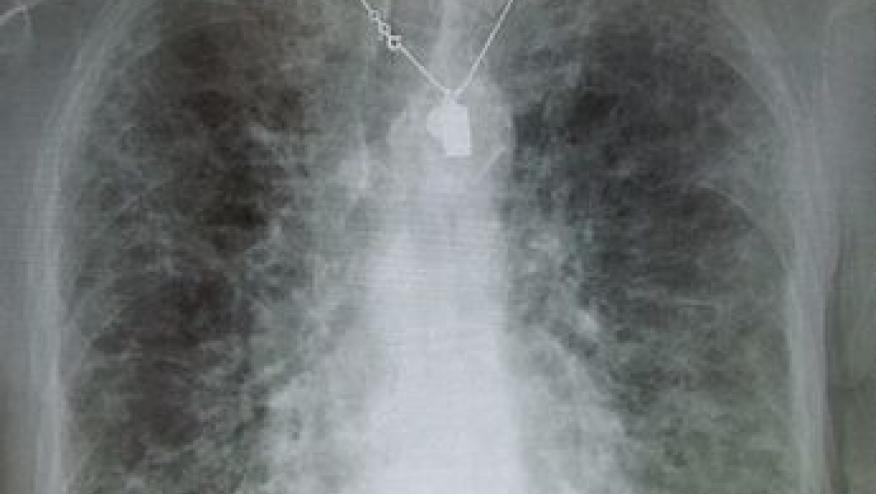

Microscopic polyangiitis (MPA) is one of several vasculitides that affects the lung. Its most common pulmonary complication is diffuse alveolar haemorrhage, which carries a significant morbid risk. MPA association with pulmonary fibrosis (PF) has been increasingly reported. Do MPA patients with PF have different characteristics and evolution to those of MPA patients without PF?

In the retrospective review of 28 patients, high prevalence of pulmonary fibrosis in MPA patients (32%) was observed and most of MPA-PF patients had a poor outcome as compared to non-PF group. PF was often the first manifestation of the disease.